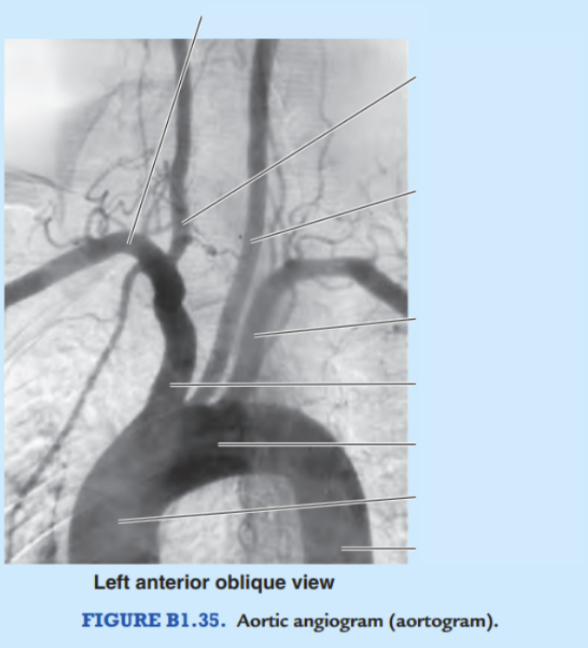

Label the arteries